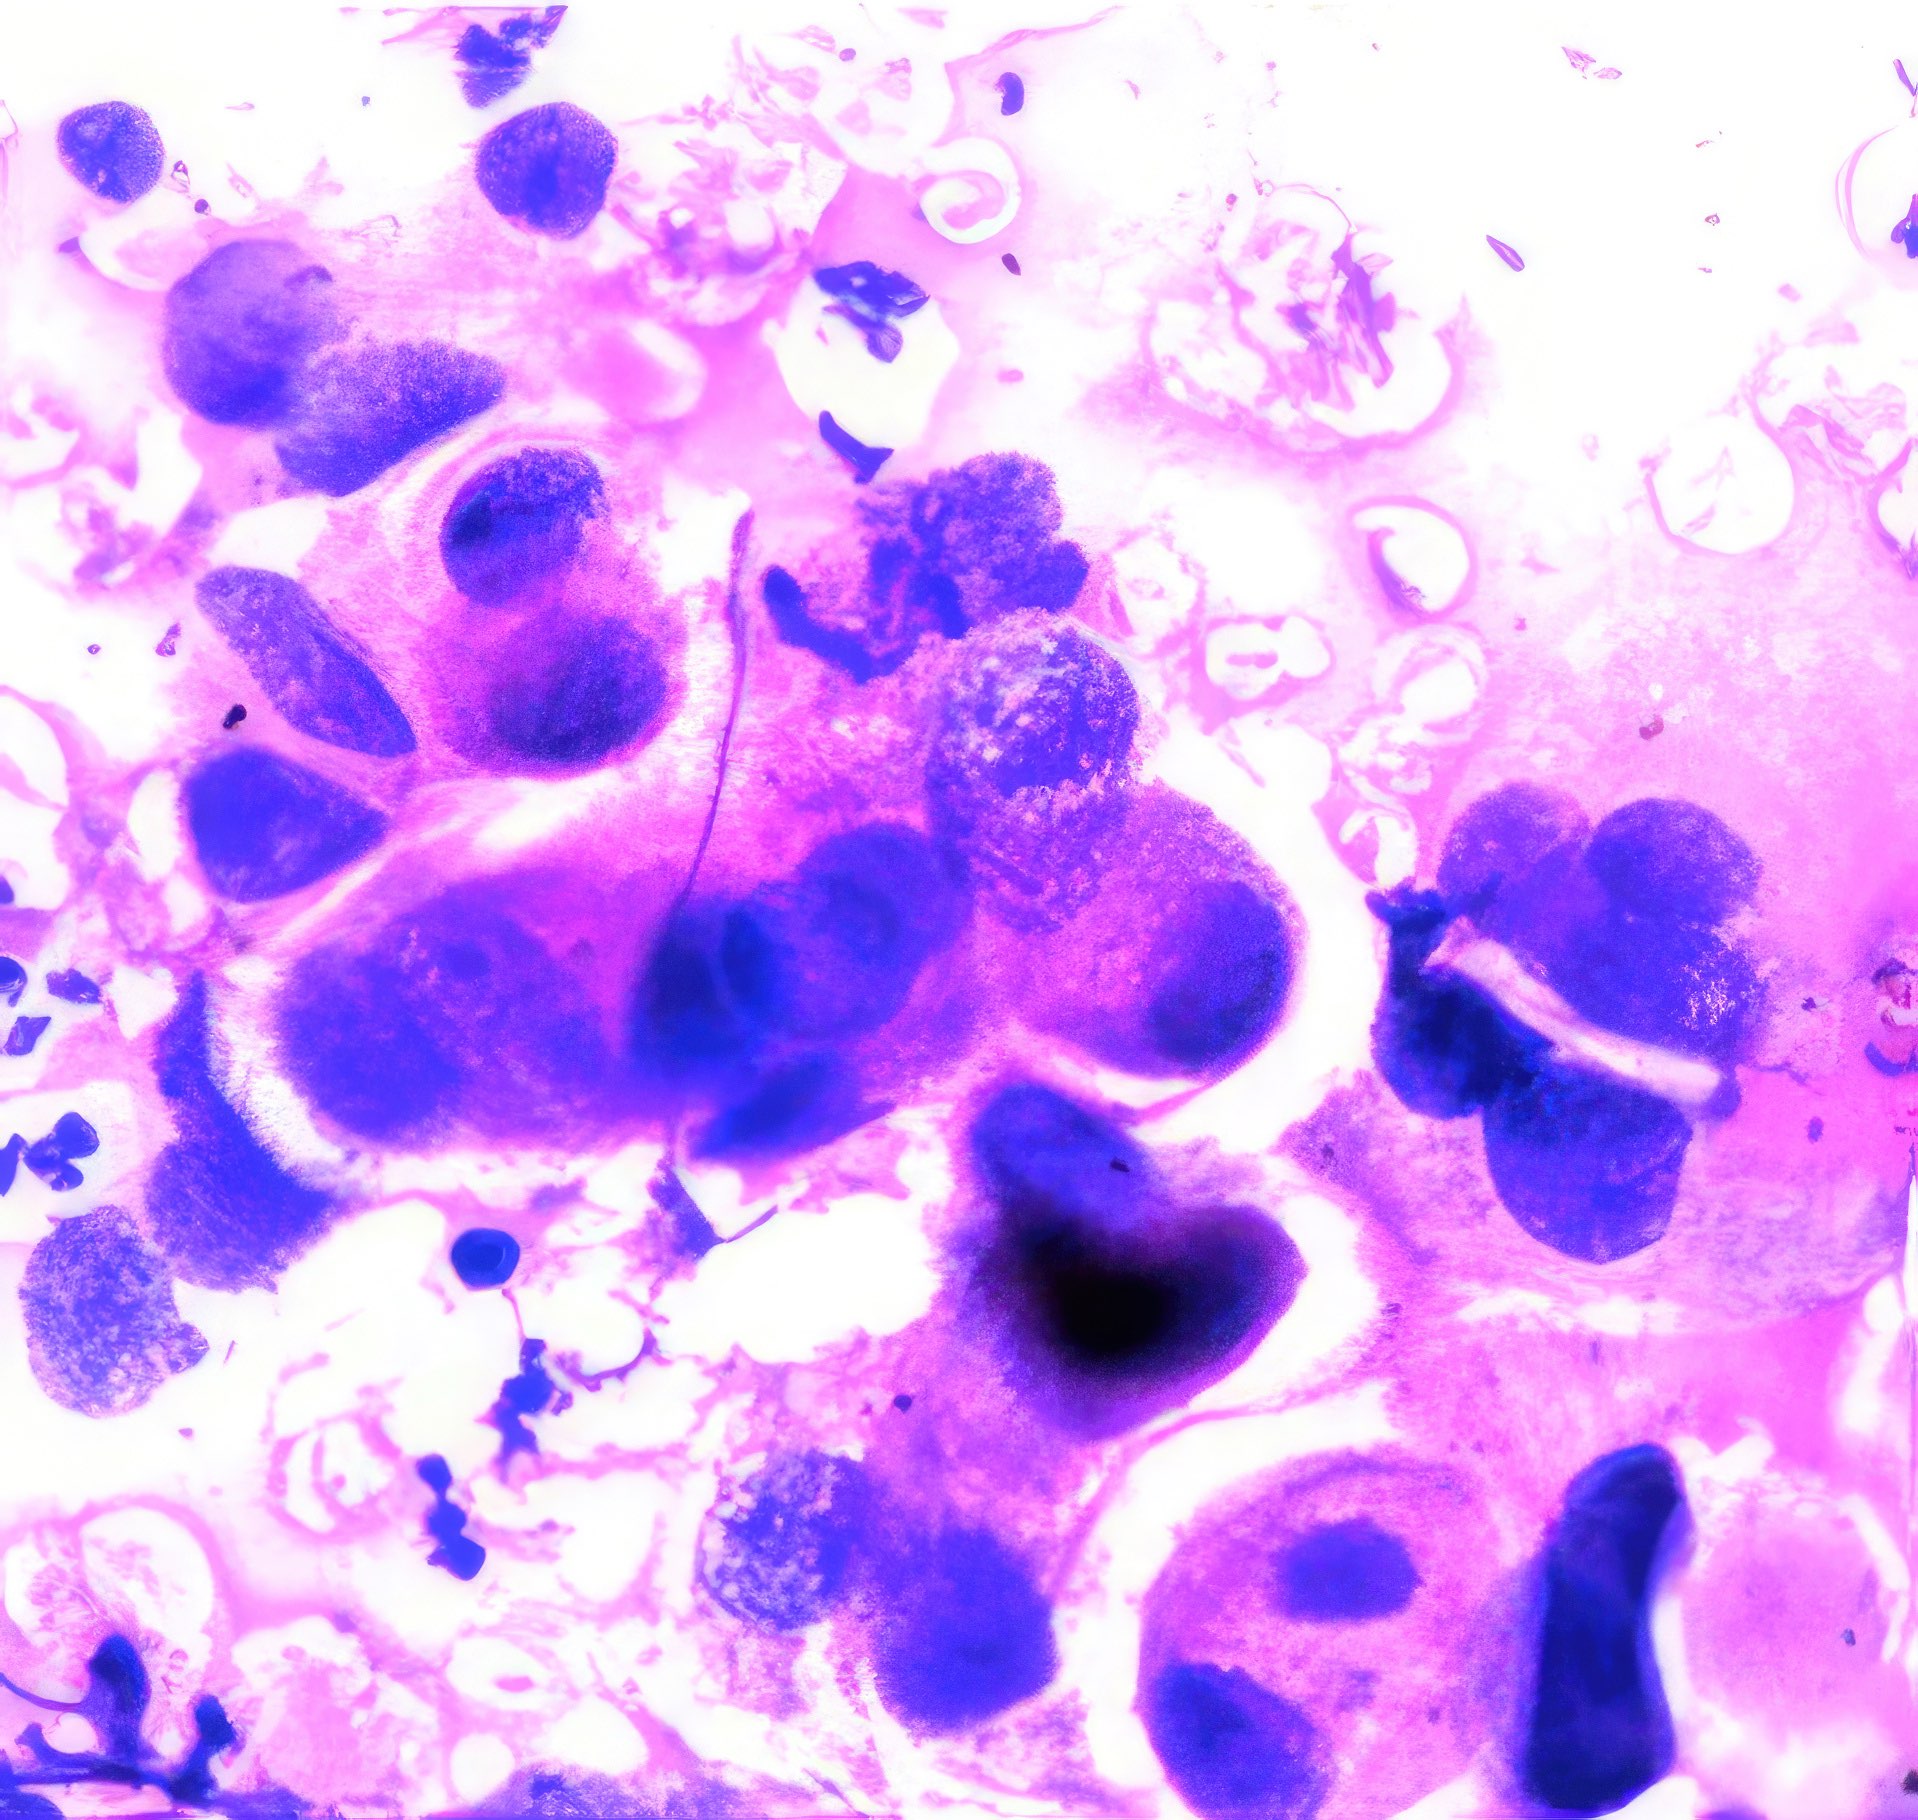

M, 55 Jahre, bemerkte seit 3 Monaten eine zunehmende inguinale Lymphknotenschwellung, der größte 3 x 4 cm messend, davon Feinnadelaspiration (FNA). Abbildung 1 bis 4: Verschiedene Areale des zytologischen Ausstrichs. Orig. 63x

Beschreibung

Die Bilder zeigen hochatypische Zellen. Deren überwiegend runde, teils auch ovalen Kerne variieren erheblich in ihrer Größe, sind deutlich grob strukturiert und enthalten meist ein oder mehrere prominente Nukleolen bzw. Chromozentren. Das Zytoplasma erscheint fragil. In jedem Bild finden sich auch Zellen mit pigmentbeladenem Zytoplasma. Der Ausstrichhintergrund enthält Blut und Zelldetritus, ebenfalls vermischt mit Pigmentkörnchen.

Kommentar

Der Patient beobachtete seit einem Jahr am Fuß eine pigmentierte Veränderung, die seit 3 Monaten auf 3 cm Durchmesser zunahm. Die prominente Atypie und die pigmenthaltigen Zellen sowie die ausgedehnte Metastasierung in die inguinalen Lymphknoten sind typisch für das Melanom. Eine Verwechslung des Melanin-Pigments mit Hämosiderin ist wegen der Zellatypie so gut wie ausgeschlossen. – Amelanotische Melanome zeigen oft eine weniger ausgeprägte Kernatypie und sind eher mit einem anderen Tumor zu verwechseln.